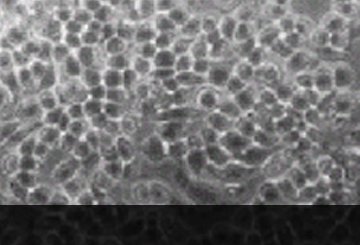

봉독투여 전 염증세포